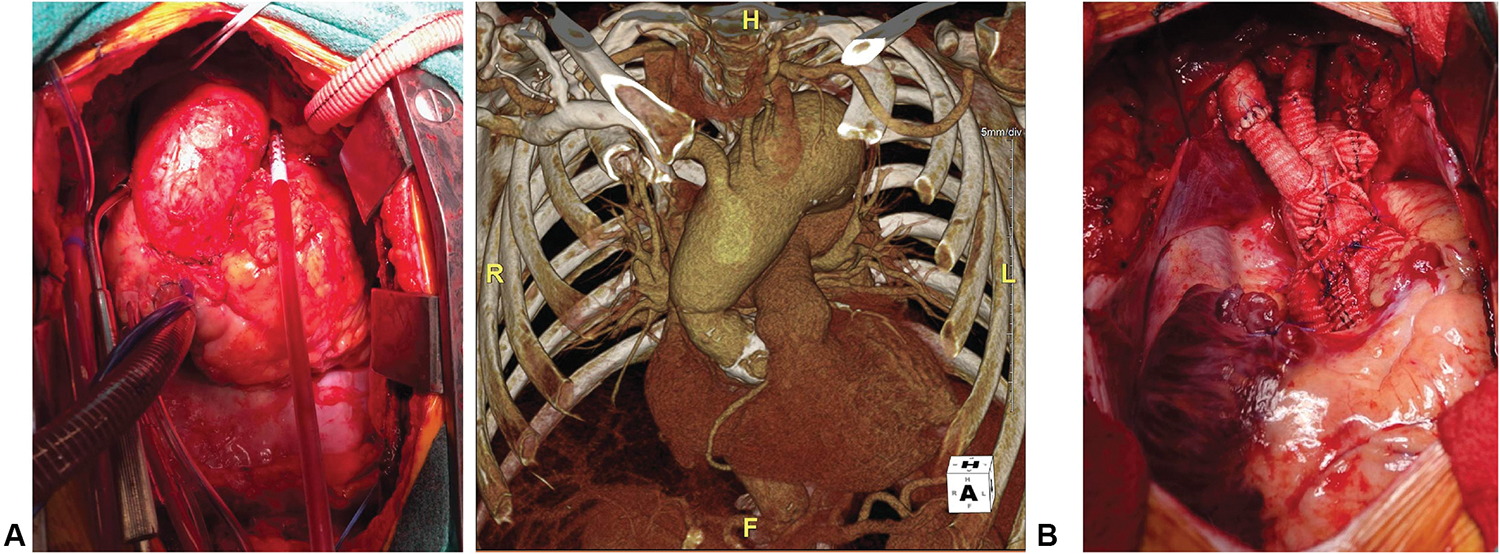

FIGURE 1.

A, Spontaneous late arch aneurysm in patient with LDS. B, Concurrent VSARR and arch replacement.